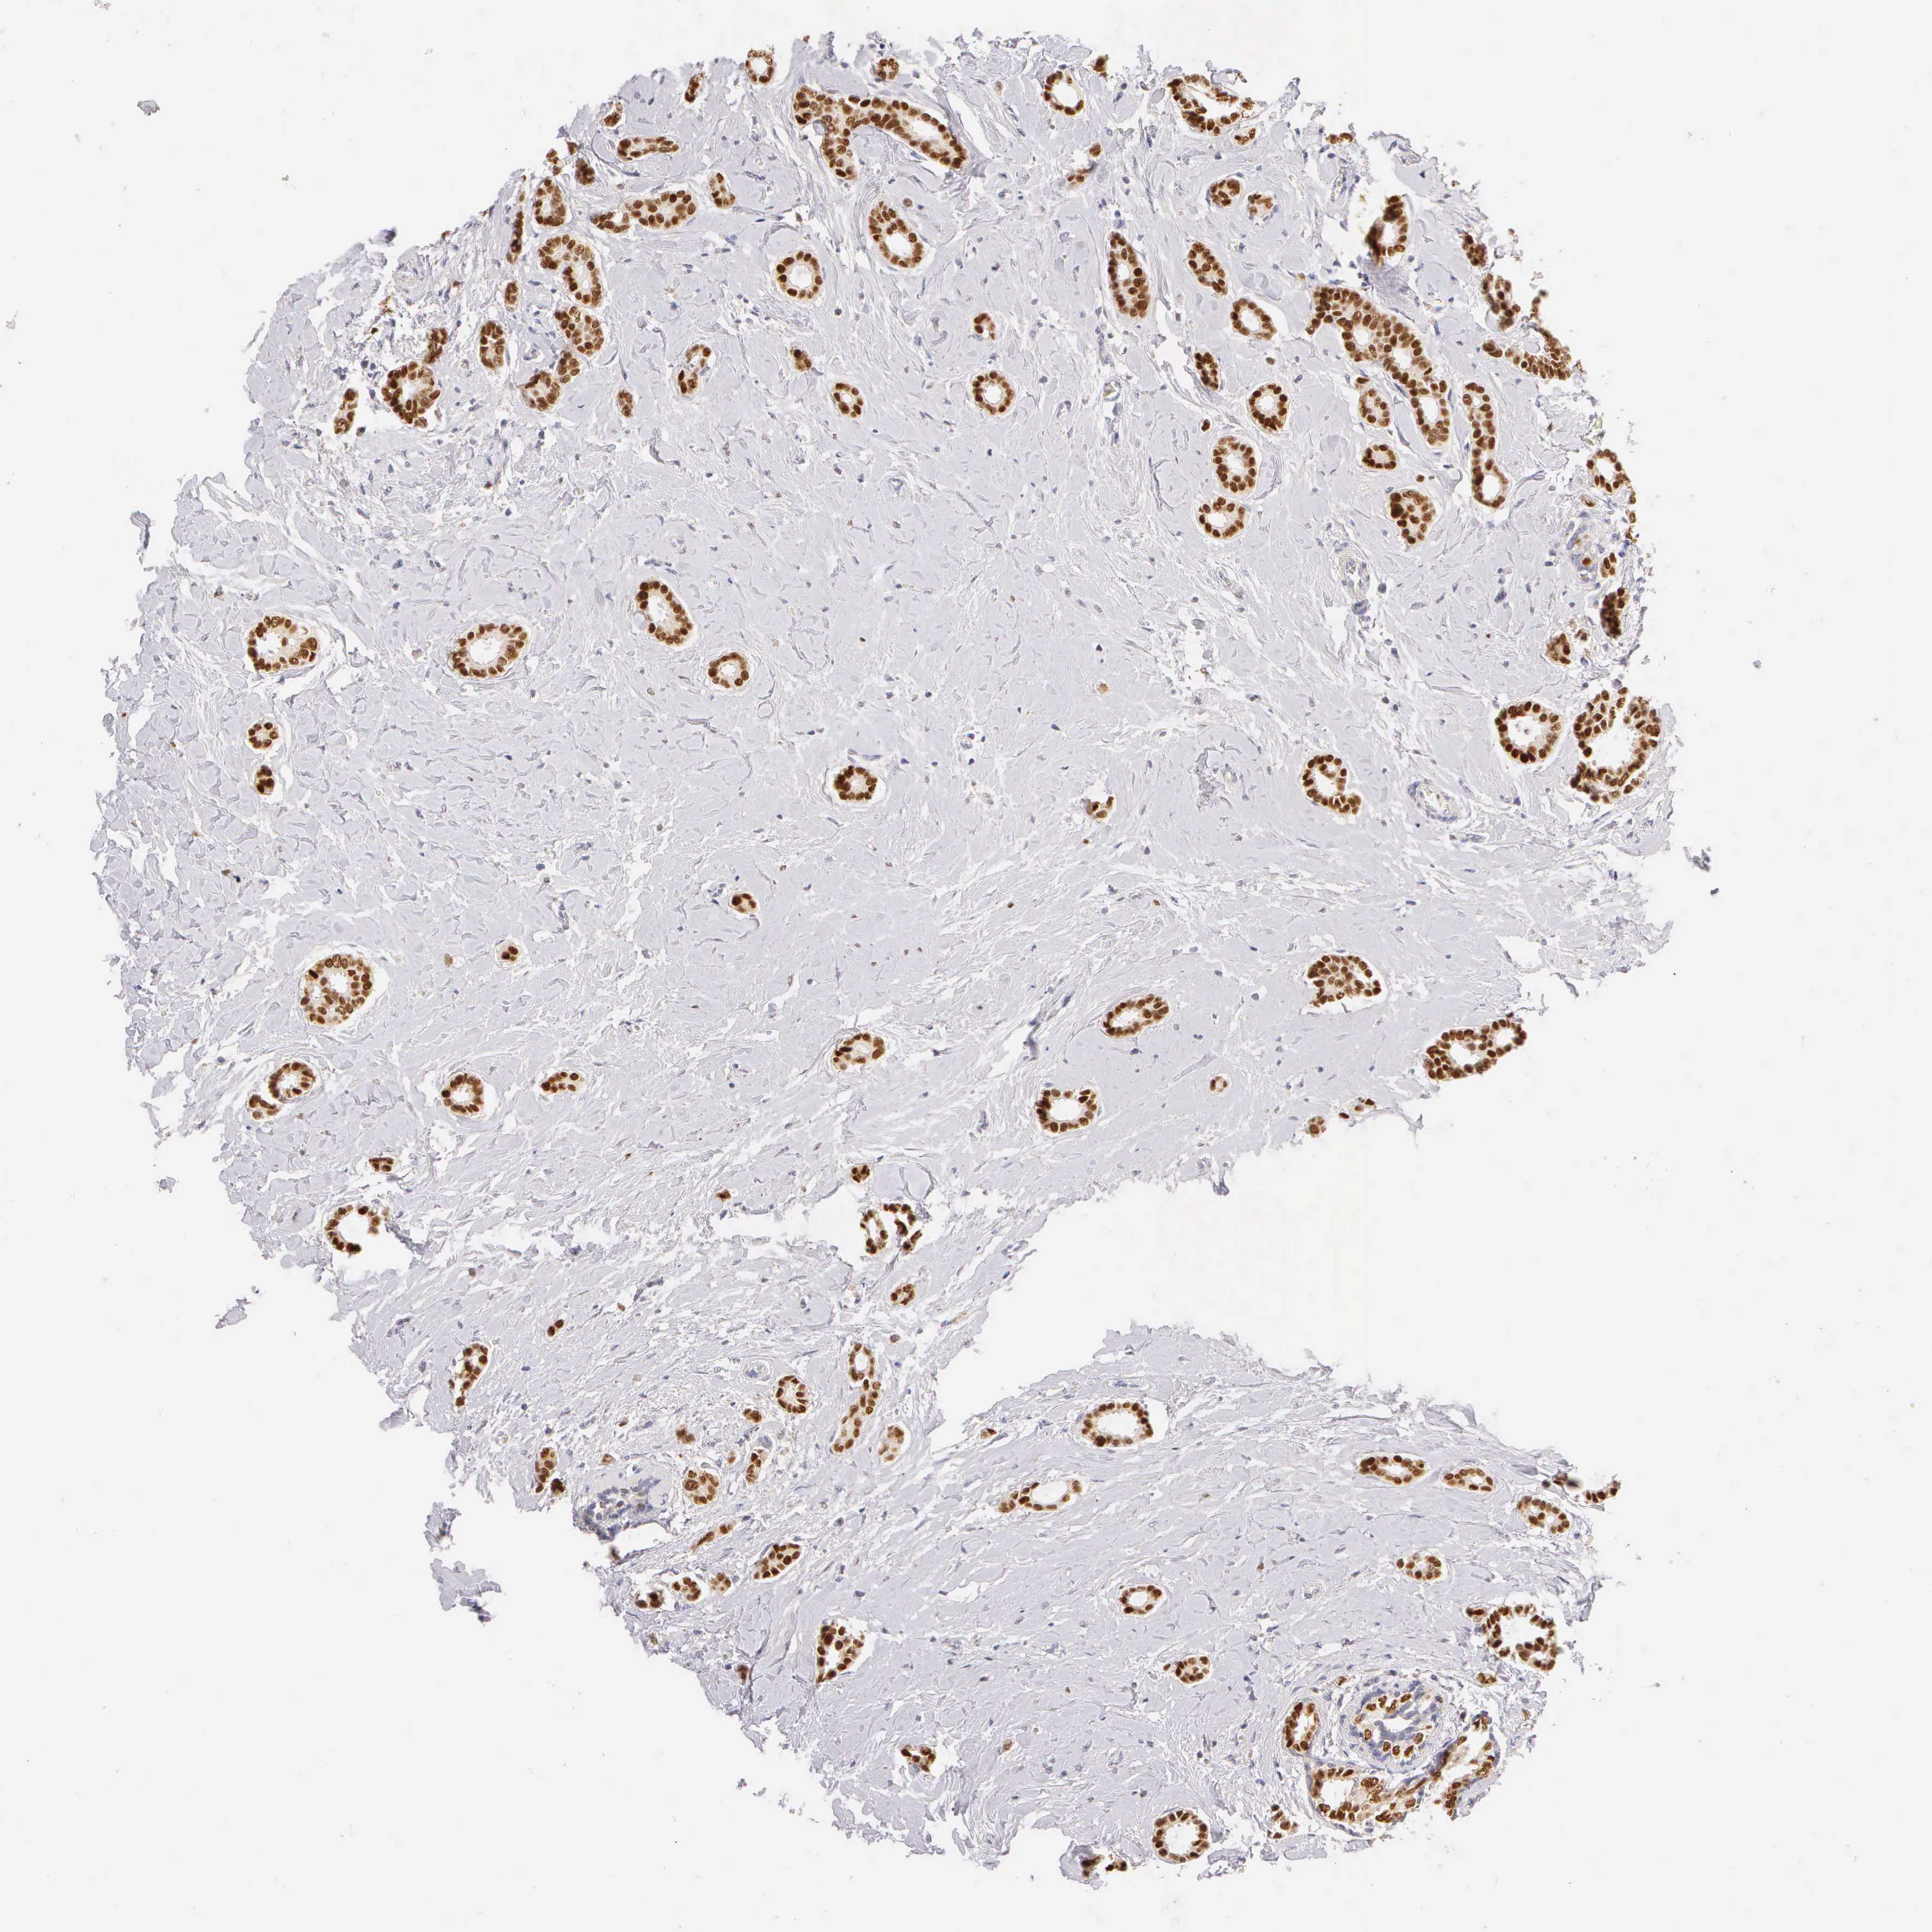

CANCER BREAST CANCER Show tissue menu

BRCA TCGA BRCA VALIDATION PROTEIN EXPRESSION

ANTIBODIES

AND

VALIDATION